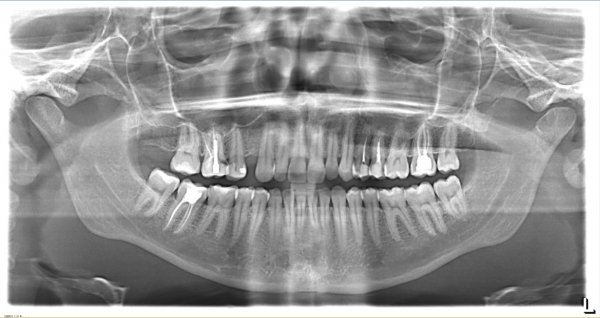

Проблема в следующем: появился свищ между 5 и 6 зубом сверху, сходила на рентген, на снимке видно затемнение корня 6-го зуба. Рентгенолог сказала, что похоже на гранулему. Пошла на консультации к врачам, итог такой — один врач сказал никто не возьмется перелечивать, зуб проще удалить (город маленький, специалистов не так много), хотя пролечено хорошо все. Второй врач сказал, что пролечено плохо, надо все убирать и лечить заново минимум полгода. Третий врач сказал, что есть смысл перелечить только тот канал, над которым гранулема, так как остальное пролечено хорошо...

Теоретически, пролечить данное воспаление можно, на это потребуется современное оборудование и ваше терпение, так как данное лечение возможно продлится более 6 месяцев. Смысл лечения данного канала — это закладывание лекарства на верхушку корня, своевременная смена и наблюдение за динамикой. В общем удалять пока не спешите, попробуйте полечить, но вы должны знать, что все абсолютно индивидуально и лечение совершенно не гарантийное.

Перелечивать необходимо все три канала, так как на двух остальных также имеется воспаление. Вам необходимо обратиться к терапевту с хорошими знаниями эндодонтии.